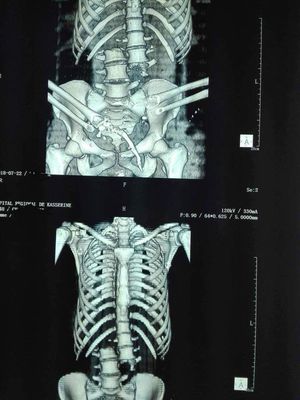

Sectioned spinal cord

Completely secioned spinal cord due to an accident Dead patient

Wow, a photo of this would've been gory. You can see in the top photo, this guy lost his 2 hands almost entirely. What a horrific way to go.